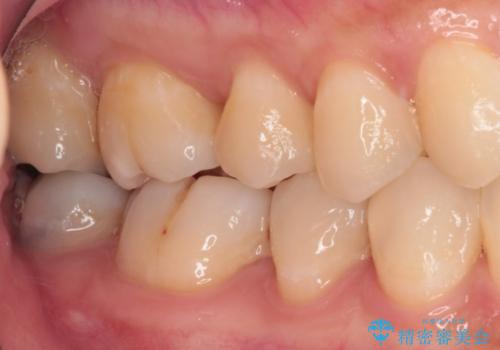

精度の高いセラミックインレーによる修復治療を行うこととしました。

処置を行った歯以外にもむし歯と思われる歯が多数ありますが、費用のかかる治療であれば、優先順位をつけて、処置を急ぐ歯から処置を進めて行きました。